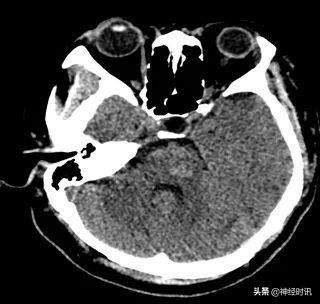

住院2周,口服脑血疏12 d复查CT:脑干出血治疗后改变,出血基本吸收